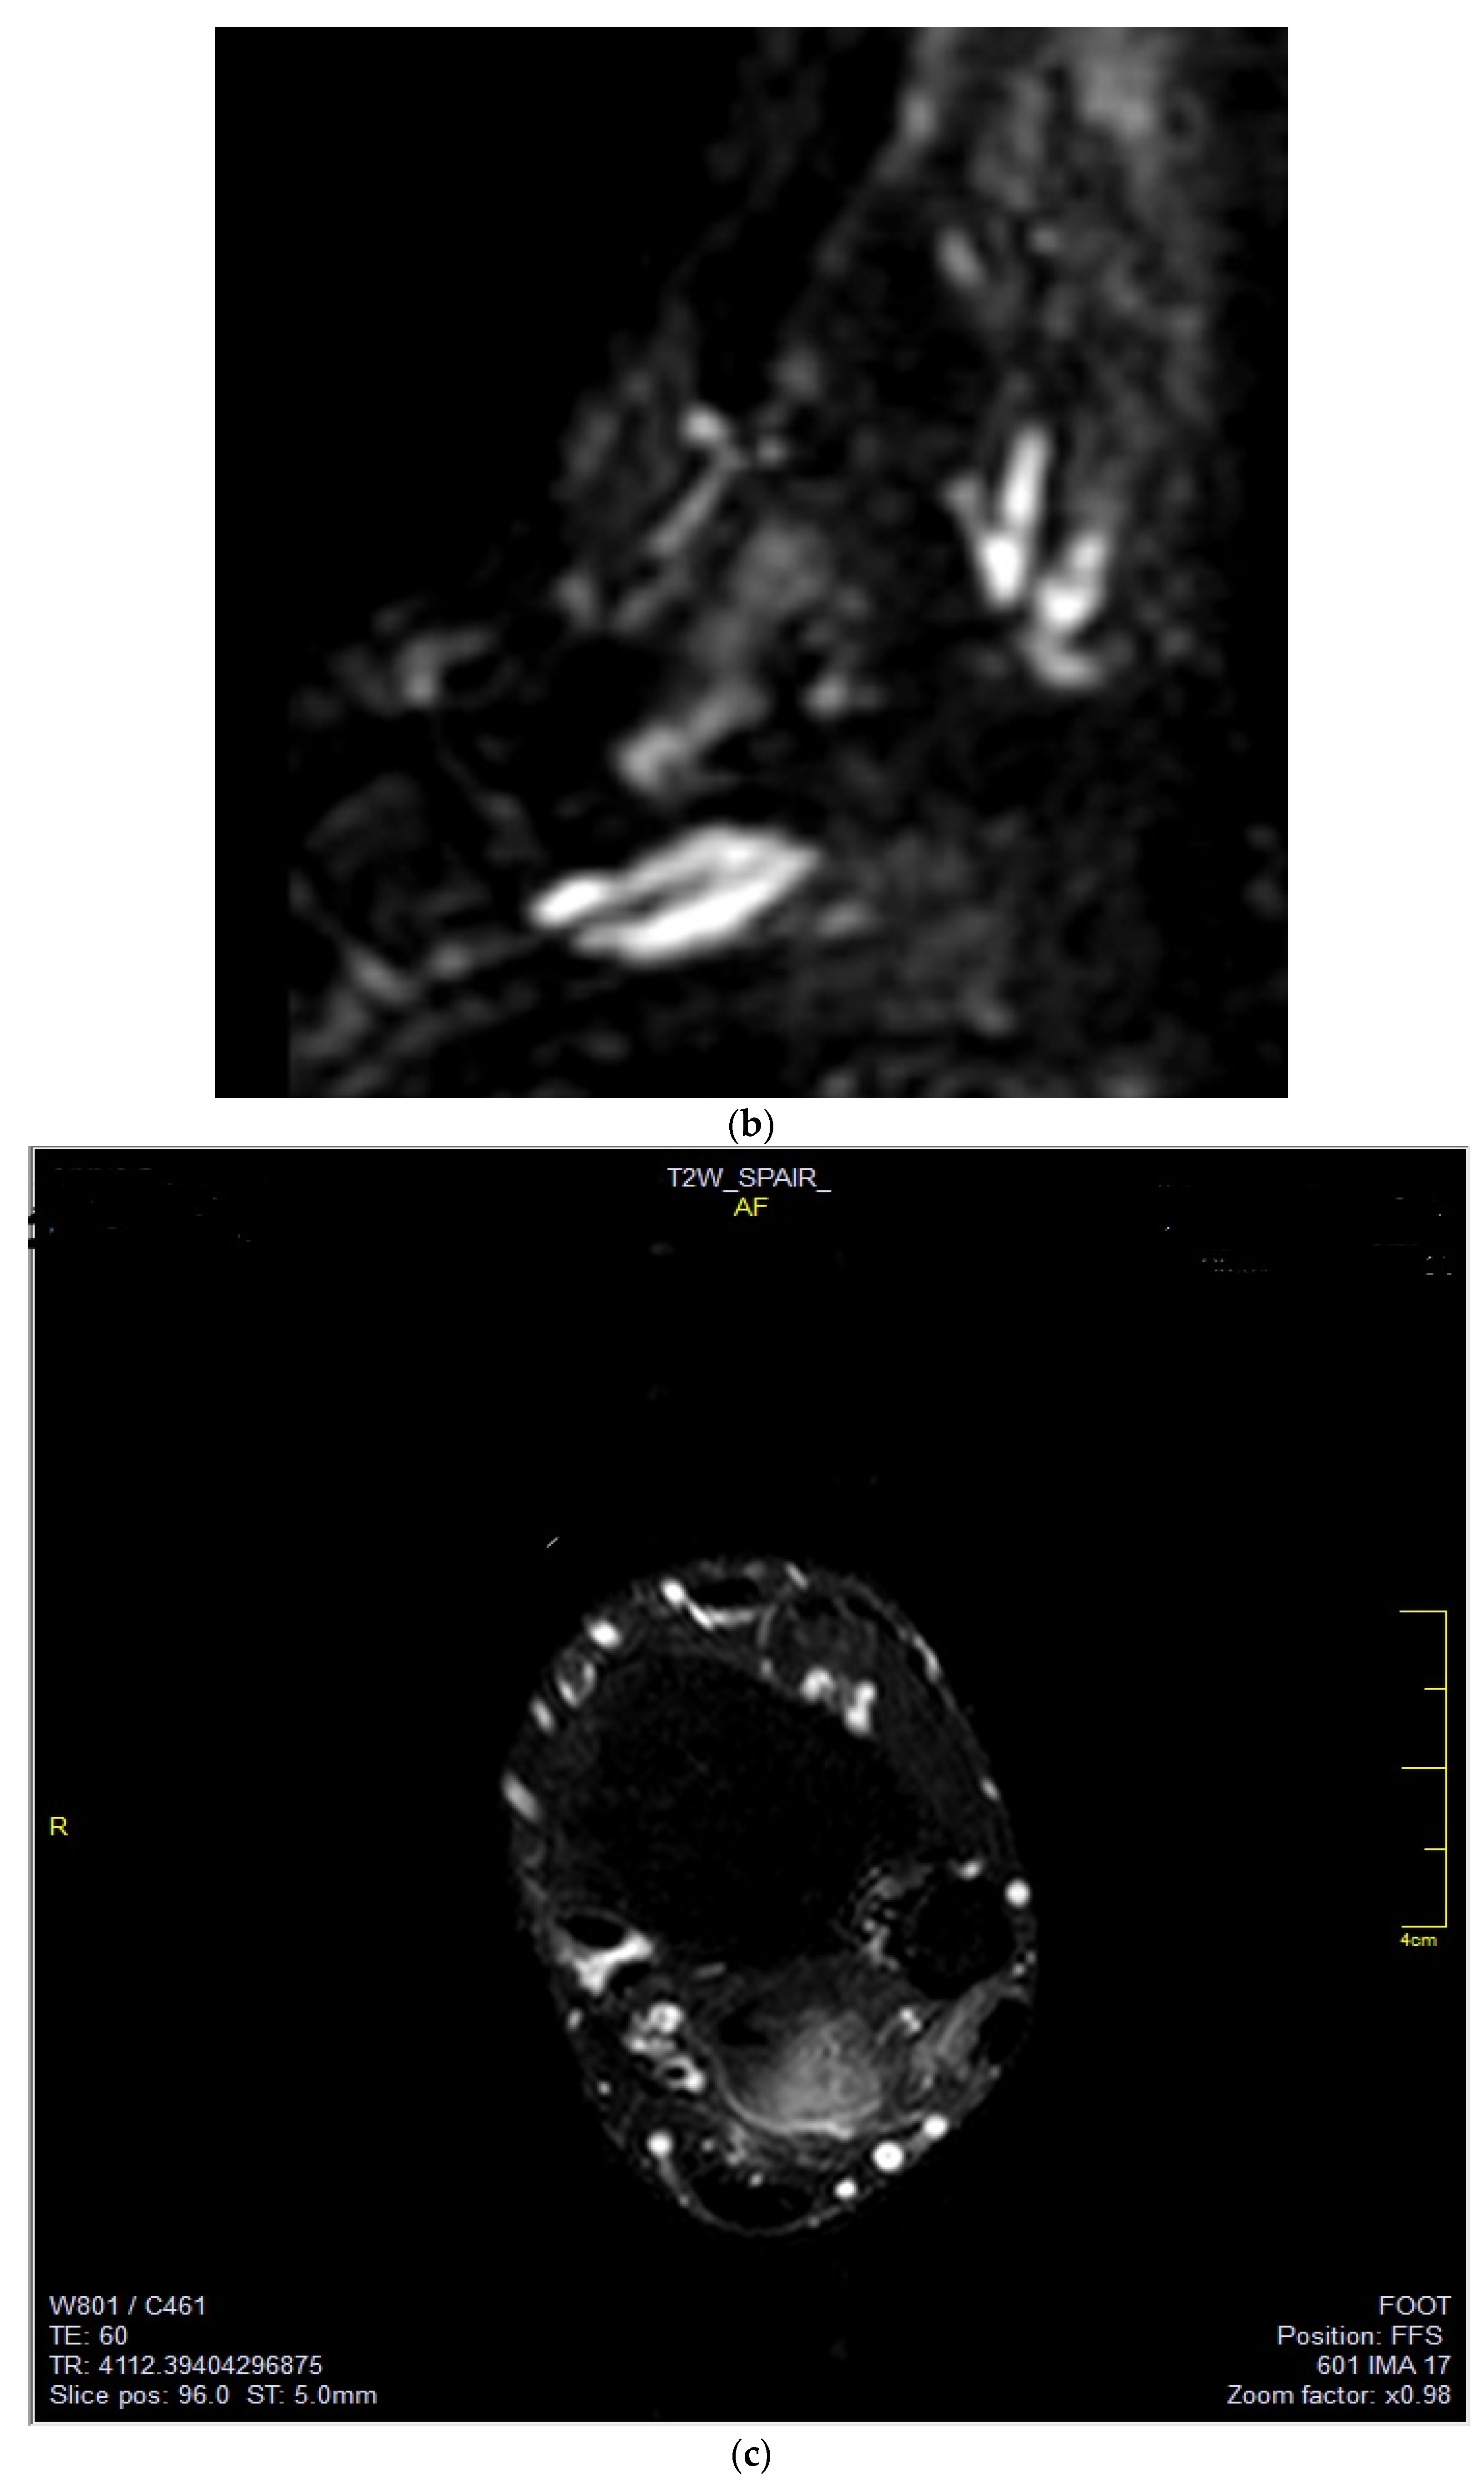

Figure 3.

(a–c) Sagittal T2WI, coronal DWI, axial T2WI images. The images depict an FDL tendon partial tear.